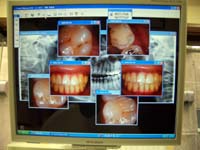

<デジタルレントゲン>

従来型と比べ、大幅に被曝量を抑えております。

デジタルなので、現像までの時間も短く、鮮明な画像により、さらに正確な診断が可能です。

患者様は、チェアーにお座り頂いたままで、ご自身の鮮明なレントゲン画像をご覧になる事が出来ます。

(上記画像の掲載につきましては、患者様よりご了承を頂いております)

<口腔内カメラ>

ご自身の歯及びお口の中はなかなか見えないものです。

そこで当院では、口腔内カメラを導入しております。

治療前及び治療後にご自身のお口の中をご覧頂き、真にご納得頂ける治療をご提供しております。

チェアーにお座り頂いたままで、ご自身のお口の中の画像をご覧いただけます。(右上のお写真)

尚、上記画像の掲載につきましては、患者様よりご了承を頂いております